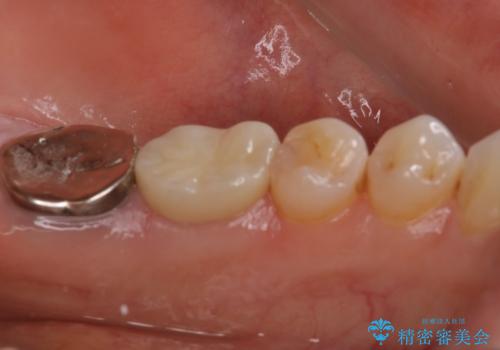

他院で仮歯までしたが、放置していたためセラミック入れたい セラミック治療

- 他院で、仮歯にしたがセラミックの値段が高すぎると思ったため治療相談も含めて来院された患者様です。

仮歯を新調させていただき、再度虫歯治療を行なって、歯の形を作りセラミックを入れさせていただきました。

フルジルコニアクラウン 7万円(税抜)

仮歯 1万円

にて治療させていただきました。色に関しても喜んでいただき満足されていました。